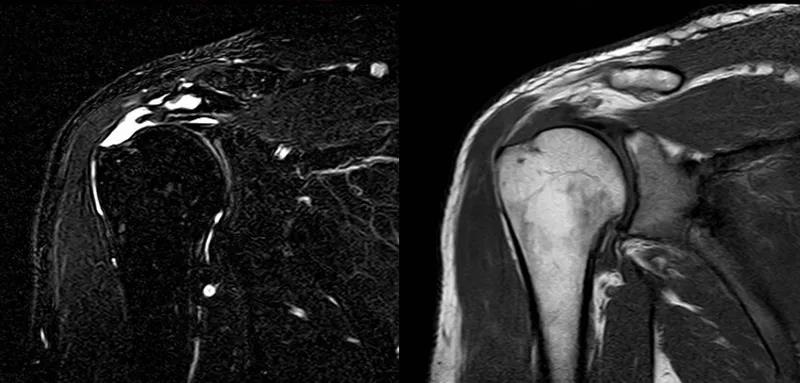

图25 巨大肩袖损伤(冈上肌)